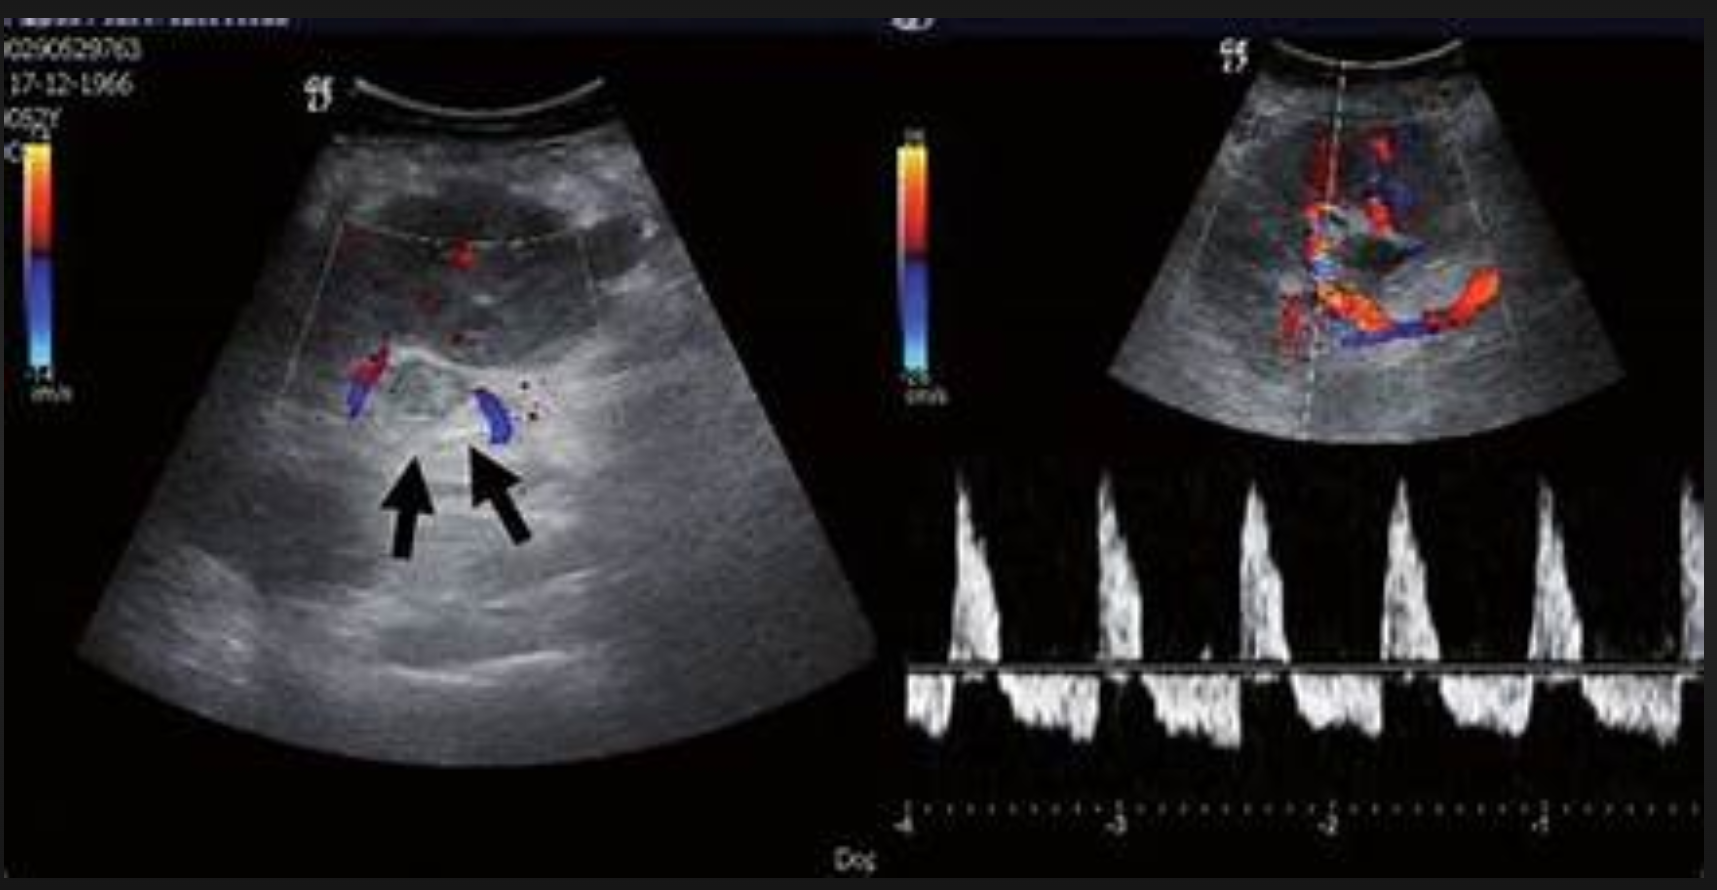

Sono findings of renal vein thrombosis (3)

- heterogenous, enlarged kidney

- enlarged renal vein

- absent doppler